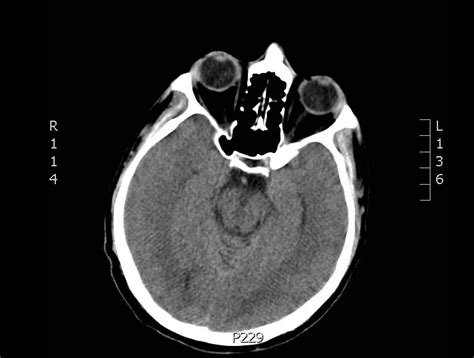

Interpreting a Normal CT of Brain

Interpreting a normal CT of brain involves looking for specific features that indicate the absence of abnormalities. Key elements that radiologists examine include:

• Brain Tissue: The brain tissue should appear uniform and without any signs of swelling, bleeding, or tumors.

• Ventricles: The ventricles, which are fluid-filled spaces within the brain, should be of normal size and shape.

• Blood Vessels: The blood vessels should be clear and free of any blockages or aneurysms.

• Skull and Bones: The skull and surrounding bones should be intact and without fractures or other abnormalities.